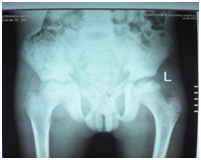

A 12-year-old boy was diagnosed with Sickle Cell Disease (SCD) with genotype SS about one year prior to. He presented with 2 months history of inability to walk and pain in both legs to Komfo Anokye Teaching Hospital in Kumasi, Ghana. The complaints were associated with marked weight loss and generalized body pain. He had been admitted about 2 weeks prior to the onset of current symptoms on account of abdominal pain and anaemia where he was haemo-transfused, given medications and subsequently discharged. There were no other significant findings in the past medical history, immunization history, nutritional and developmental histories. On examination he was found to be wasted (Weight for Height z-score <-3SD), pale, afebrile and anicteric. He had palpable axillary and inguinal lymph nodes (each measuring about 1cm to 1.5cm, mobile, non-tender and not matted). Vital signs were normal on admission. Other significant examination findings were obvious swelling of the right leg which was warm to touch, erythematous and tender on palpation. He had a gibbus deformity of the lower thoracic spine with no remarkable neurological findings in the lower limbs. A diagnosis of SCD with vaso-occlusive crises and cellulitis of the right leg was made with differential diagnosis of osteomyelitis, Deep Vein Thrombosis and Potts disease. Initial investigations revealed WBC of 13.51 X 109/dl with Neutrophils 8.83 (65.3%) Lymphocytes 4.27 (31.6%) and Monocytes 0.25(1.9%), Hemoglobin 7.1g/dl, MCV-70.7, MCH-22.4, Platelets: 538, ESR-117, INR-1.05, Prothrombin Time-14.3secs and blood sugar-6.5mmol/L. Malaria parasites were not seen on the blood smear and patient was negative for Retro-Viral Screen for HIV. Other investigations included Doppler Ultrasound, Chest X-ray, Pelvic x-ray, Thoraco-lumbo-sacral spine X-ray (Figure 1-10). Blood culture and sensitivity could not be done at the time of admission as microbiology service in the hospital had a brief logistic challenge. Radiological findings revealed the following: Reduction in the vertebral body heights of T7-T10 with associated reduction in the intervertebral disc spaces and crowding of the posterior ribs. A paravertebral soft tissue mass extending from T4 vertebral level to T11. Coarse trabeculation and sclerosis of the ribs noted. Expansion of the anterior end of the left 8th rib with ill-defined lytic areas. Buckling of the cortex of the lateral aspect of the left 9th rib, suggestive of a fracture. The imaged portion of the proximal humerus shows periarticular osteopenia. Also noted was relatively small left humeral head with left glenohumeral joint space. There are patchy homogenous opacities in both lung fields predominantly in the lower zones. There was associated silhouetting of the hemi diaphragms bilaterally and the cardiac shadow. There was generalized sclerosis of the imaged pelvic bones with coarsening of the trabeculae. The right femoral head was deformed and expanded with sclerosis and lytic areas within. There was associated narrowing of the right hip joint space. The left femoral head also showed patchy lucencies. No deformity of the left femoral head seen. The left hip joint space appeared normal. Also noted was fusion of the sacroiliac joints bilaterally. There was diffuse sclerosis of the imaged vertebrae with coarse trabeculae. The vertebral endplates of L1/L2 and L3/L4 showed sharp depression at the margins with a flat base centrally giving it the H shaped appearance. Also noted were ill-defined lytic areas in the L3 to L5 vertebrae with associated end plate irregularities and reduced intervertebral disc spaces at L3/L4 and L4/L5. No paravertebral soft tissue mass seen. No fracture or listhesis seen. Changes of the thoracic spine were described under the chest x-ray.

These radiological diagnostic features were suggestive of sickle cell disease with Thoracolumbar spondylodiscitis, likely pyogenic; Bilateral Avascular Necrosis of the femoral head (early on the left); Septic arthritis of the right hip and left shoulder joint; Osteomyelitis of the left 8th and 9th ribs. Doppler Ultrasound of the lower limb revealed the following: The right common femoral and superficial femoral veins were of normal lumen with good wall to wall compressibility, good colour doppler and spectral wave form properties. The right popliteal and posterior tibial veins however showed extensive echogenic intraluminal-filling defect with resultant loss of wall-to-wall compressibility (percentage stenosis 76%). The accompanying arteries were of normal size and caliber and showed good colour doppler and spectral properties. There was thickening of the subcutaneous tissue with dilated fluid channels seen in the right foot. Inguinal as well as popliteal lymph nodes with retention of their fatty hilum noted averaging 0.9*0.5cm. Also noted was a 1.4*0.9*1.5cm (volume about 1.0ml) anechoic collection with low-level internal echoes at the medial aspect of the proximal thigh muscles; suggestive of inflammatory changes. Based on the Doppler findings a clinical diagnosis of Right Popliteal and Posterior Tibial Vein Thrombosis with Pyomyositis in a Sickle Cell Disease patient was considered and patient was subsequently administered subcutaneous Enoxaparin 40mg daily as well as Warfarin 3mg nocte, IV Clindamycin 150mg qid, IV Ciprofloxacin. After 2 days of Warfarin and Enoxaparin, INR and PT were repeated and results were 1.1 and 15.1s respectively. The child was followed up closely for four weeks and subsequently discharge. A repeat Doppler finding revealed a completely resolved thrombus with no evidence of DVT.

Aseptic necrosis of the large bone heads is a common manifestation in the older SCD patients.25,26 The progression of aseptic necrosis is facilitated by malnutrition and secondary bacterial infections. This child presented with significant level of malnutrition (Weight for Height z-score <-3SD), osteopenia and evidence of joint space narrowing are clearly risk factors for progressive aseptic necrosis. Similar explanation above could account for the pathological rib fractures and the gibbus observed in this child. Acute Chest Syndrome (ACS) is one of the life threatening conditions of SCD and is usually confused with pneumonia in children.27,28 Clinicians should have high index of suspicion for ACS. This child did not present with ACS but radiological evidence of opacities in the lung field demonstrates past occurrence of ACS. DVT is not uncommon disease in children and cases have been reported.29,30 The occurrence of this disease is associated with risk factors such as cancers, trauma, infections, venous catheterization, sickle cell disease and coagulation disorders.29 This patient had two risk factors for DVT; Sickle Cell Disease and possible multiple infections.31 In addition to these risk factors, was the fact that this child was immobile for most of the time during the onset of the illness (suffering from septic arthritis of the hip and pyomyositis). In SCD patients, presentation with lower limb pain and tenderness is mostly associated with vaso-occlusive episodes and/or osteomyelitis in areas with high prevalence of the disease. Clinicians should have a high index of suspicion for DVT since it can occur in cases with multiple risk factors. This is critical since the occurrence of Pulmonary Embolism (PE) from the DVT will be life threatening and could also be easily confused to be ACS in a SCD patient and patient would be mismanaged. This short case report therefore tried to highlight some of the uncommon pathologies amongst others that might arise in a SCD patient and to alert clinicians to look out for DVT as an uncommon differential diagnosis in swollen limbs in these patients. It is worth noting that attention needs to be paid to a multi-disciplinary preparedness and response approach to the management of SCD patients, as presented in this case report, to mitigate or minimize disability and mortality.